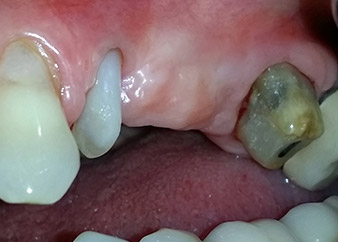

58-годишна пациентка се оплаква от болка и повишена подвижност в нейния мост върху зъб 24 с функция на абатмънт. На лице е периодонтално възпаление с дълбочина на джоба 7 mm мезиобукално и повече от 12 mm дистално, както и включена 3 градусова фуркация. Освен това, рентгенографията показва обширна периодонтална лезия около апикалната зона на (друго място) предварително ендодонтски обработен зъб 24 (Фиг. 1).

Една година по-късно, зъби 25 и 26 са екстрахирани в следствие на травма и поради ендо-перио причини, преди поставянето на моста. Комбинирана ендо-перио лезия е диагностицирана за зъб 24 от неясна етиология. Пациентката иска да задържи нейния мост с абатмънт на зъби 24 и 27 и не приема окончателна, подвижна протеза. По този начин, взаимно решихме да положим всички усилия да запазим и двата зъба, въпреки лошата прогноза за тях, която е базирана на рентгенографски и клинични резултати.

След един месец, в деня на операцията, болката и възпалението в зъб 24 е минимално, но подвижността в Miller class 2 е на лице. След отваряне на ламбата и почистването на периапикалната и перирадикуларната тъкани, обхватът на костния дефект стана очевиден (Фиг. 2 и 3).

В букалния корен, цялата вестибуларна и дистална кост липсва. Захващането е значително ограничено до палатиналния корен, подчертавайки предварително лошата прогноза. Зъб 27 също откри намалено хоризонтално захващане и минимално апикално разреждане (Фиг. 1) без клинични симптоми.

Фиг. 2 и 3: След повдигане на ламбото, един месец след ендодонтския преглед и прилагане на цялостна периодонтална терапия в цялата уста, букалният корен на зъб 24 разкри тотална загуба на кост и захват.